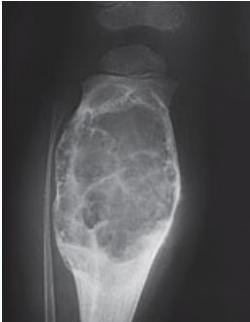

Aneurysmal Bone Cyst

- Child - young adult

- Metaphysis of long bone

- X-ray:

- Well-defined cyst

- Trabeculated

- Eccentrically placed

- Ballooning

- Bloody content

- Treatment:

- Curettage and bone graft

- Metaphysis, Eccentric

Comparison of Cyst-Like Lesions in Bone

- At metaphyseal side of physis

- Expansile